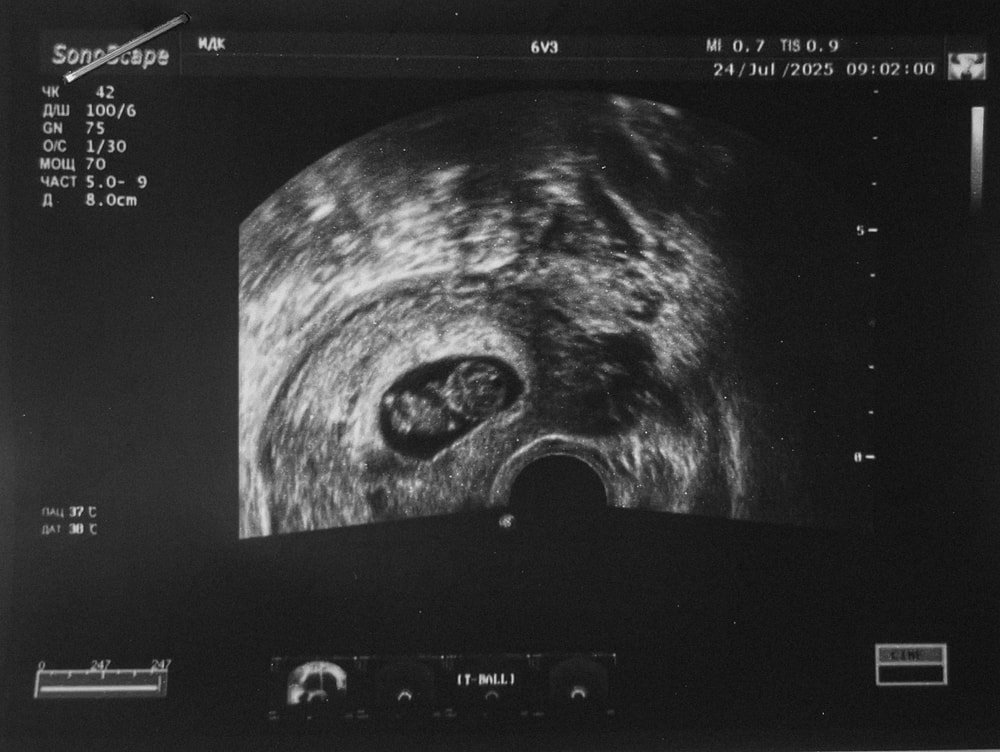

9+2. Подросло плодное яйцо!

Так переживала из-за несоответствия КТР и СВДПЯ. Динамика положительная! И хорион уже начал "облысевать".

СВДПЯ 34, КТР 25.5, уже больше разница между ними.

Результаты 6 дней назад: СВДПЯ 25, КТР 19.8.

Только вот теперь у меня новое переживание - желточный мешок 🤦♀️ Сегодня намерили 7.5 мм. Не одно - так другое, как обычно уже всего начиталась.